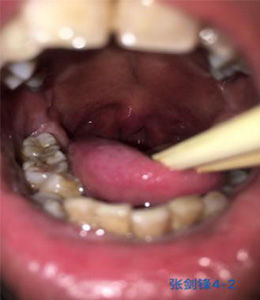

体格检查:扁桃体2度肿大、悬雍垂过长、咽腔稍狭窄、下颚后缩,舌根肥厚、舌体宽大、长厚、有齿痕.(下附图片)

| 体格检查图片1 | 体格检查图片2 | 体格检查图片3 |